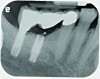

Implant related complications may be classified as minor, intermediate, major reversible/nonreversible, or major nonreversible. For example, a simple complication like a fractured abutment screw is usually considered a minor complication. It usually can be corrected with minimal cost, time, pain, and inconvenience. Treatment may be more involved for an intermediate complication such as a fractured implant (Figure 1). Up the severity scale are major complications, such as when an implant migrates into the sinus2 (Figure 2), or is exposed by mucosa and bone loss and visible to the patient a year after restoration (Figure 3 and Figure 4). Major complications may cause irreversible damage and/or require multiple procedures to try to make the patient “whole,” adding cost, time, pain, and surgeries (Figure 5 and Figure 6), and the patient may or may not receive the original restoration.

A fractured implant is classified as an intermediate complication

Figure 1

The implant of the patient shown in Figure 8 demonstrated all three of the red flag situations: it was placed too far buccally, had inadequate bone and soft tissue at the time of implant placement, and lost bone and soft tissue post implant placement. Correcting this required increased time, cost, and surgeries (Figure 9).

A implant restoration with a buccal dehiscence of bone and soft tissue caused by poor implant positioning, lack of keratinized tissue prior to implant placement, and soft tissue recession post implant restoration.

Figure 8

The same implant in Fig 8, 7 years following treatment, which included two autogenous connective tissue grafts and a bone augmentation surgery with a combined allograft and xenograft mixed with two biologics.

Figure 9